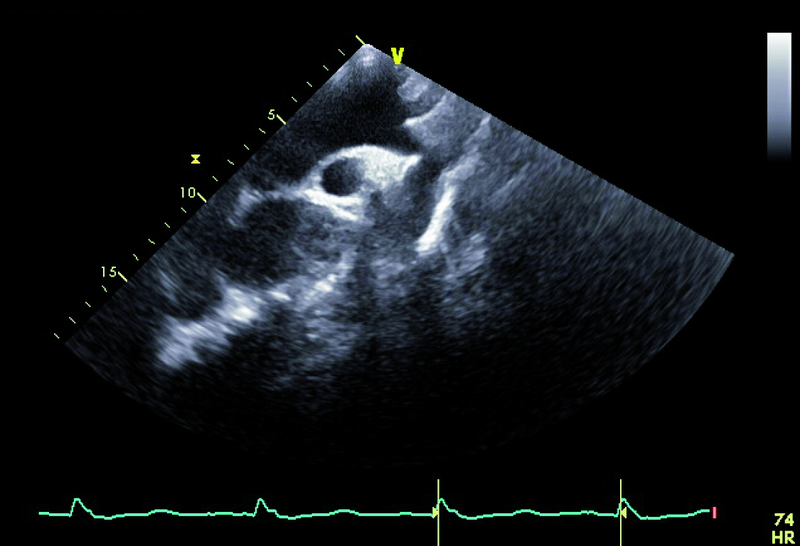

Kobieta, lat 41. Jakie patologie można rozpoznać na zamieszczonych rycinach?

1. Koarktacja aorty (ryc. 1).